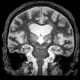

A coronal magnetic resonance imaging section shows a high-intensity focused ultrasound lesion in the left thalamus of the brain.

In 2016, the Food and Drug Administration approved a new treatment for tremor disorders in which physicians use HIFU to burn away a targeted portion of the thalamus, the brain region where many types of tremors originate. Six years later, Dr. Shah and his colleagues reported a new technique that significantly improved HIFU targeting for this treatment. Recently, the team realized that the controlled brain injury caused by this therapy looks indistinguishable from stroke in brain imaging – the two types of damage have several features in common, including how the brain responds to these injuries, Dr. Shah said.